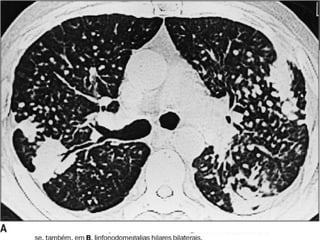

 o padrão radiológico é caracterizado por infiltrações

alveolares difusas, progressivas, às vezes com nodulações

mal definidas;